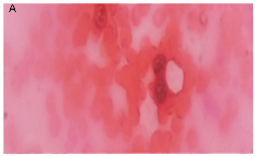

A 12 yrs old female presented to the Ophthalmology OPD with left infraorbital swelling for a period of 6 years. She also complained of intermittent epiphora. External local examination revealed a diffuse, soft, and nontender swelling in the Left infraorbital region. Pressure over the mass produced a reddish mucopurulent discharge from the lower punctum. The overlying skin was normal. The vision and the extra ocular movements were normal. The patient was from North eastern part of India. A computed tomography scan of the par nasal sinuses revealed a hyper dense lesion in the subcutaneous plane of left infraorbital region. Fine needle aspiration report was no conclusive. The Gram stain of the mucopurulent discharge from the lower punctum collected by a sterile swab after applying pressure over the lesion revealed, thick walled sporangia, with endospores suggestive of Rhinosporidium seeberi (Figure 1).

Figure 1 Gram stains showing thick walled sporangia with endospores.